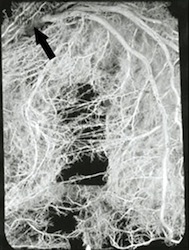

Was bedeutet diese Bilanz? Im Gegensatz zu den Herzspezialisten zieht der gesunde Menschenverstand daraus den Schluss, dass das Legen von Bypässen um koronare Engstellen offenbar kein sehr sinnvolles Unternehmen ist. Und es drängt sich die Frage auf, die unter Fachleuten so gut wie niemand zu denken oder gar auszusprechen wagt, ob denn den verstopften Kranzgefäßen tatsächlich ein derart bedeutender Stellenwert in der Entstehung eines Herzinfarkts zukommt wie gemeinhin angenommen. Des Rätsels Lösung besteht darin, dass der Organismus um die hochgradigen Gefäßengpässe Umgehungskreisläufe bildet und somit über ein natürliches Bypass-System im Herzmuskel verfügt. Die Natur weiß sich sehr gut zu helfen. Immer dann, wenn der Blutstrom in den Kranzarterien durch eine starke Einschnürung leidet, bildet der Körper ein ganzes Bündel an neuen Gefäßbahnen, die die Enge seitlich passieren. Dieses dichte Gefäßnetz verhindert, dass die Durchblutung des Herzmuskels durch die Engstelle Schaden nimmt. Ein operativ gelegter Bypass kann an diesem natürlichen Bypass-System nichts verbessern. Im 3. Kapitel gehe ich ausführlich auf diese Zusammenhänge ein.

Natürliches Bypass-System

bei Kranzgefäßverschluss (Pfeil)